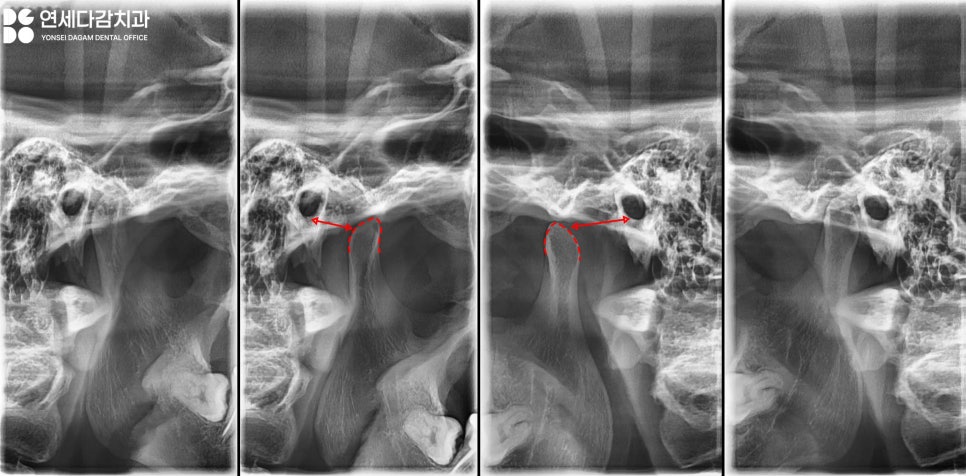

그 다음 턱관절(TMJ)용

엑스레이를 촬영하여

확인해 봤을 때는

개구량이 낮은 것을

알 수 있었습니다.

송파동 치과 에서 추가 진단을 위해

TMJ 부위에 손가락을 누른 채

관절 검사를 시행했습니다.